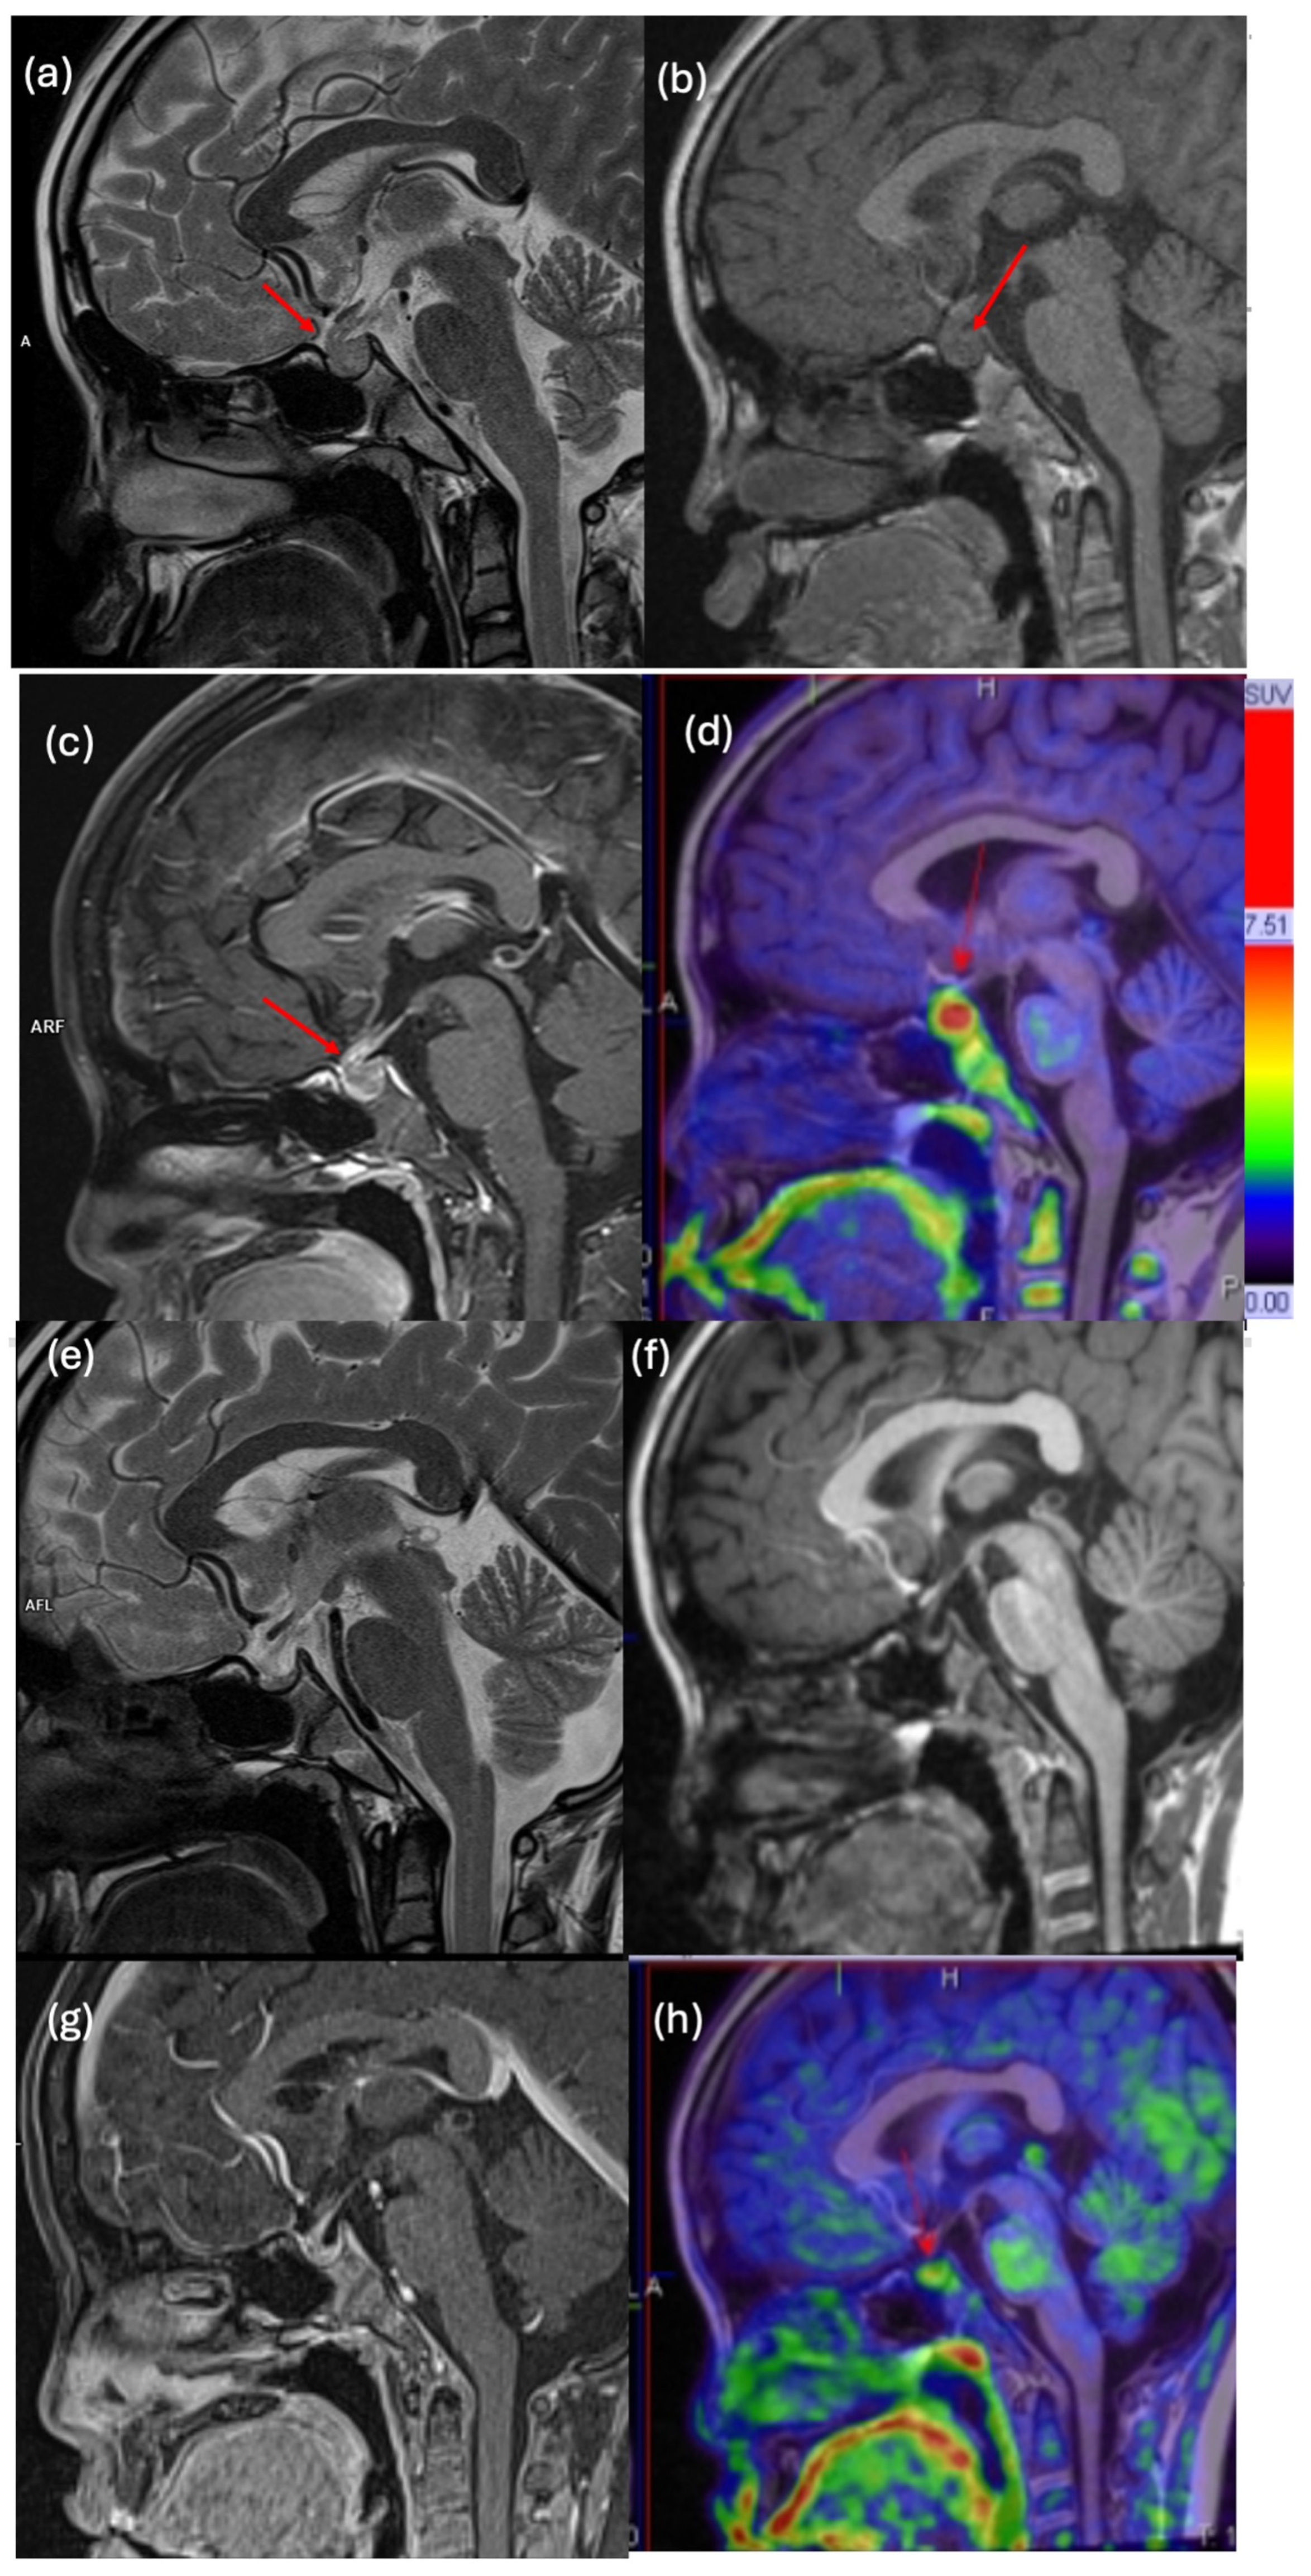

| 1 | M | 17 | Bifocal germinoma (Pineal, suprasellar, multiventricular) | M | <3 | 66 | <3 | 1 | 4 cycles VP/C + WVI + PB | Relapse | Dx | 5.5 | 3.93 | 26 |

| 2 | M | 14 | Suprasellar germinoma | M0 | <3 | <1 | <3 | <2 | 4 cycles VP/C + WVI + PB | CR | Dx | 9.55 | 5.72 | 29 |

| 3 | M | 11 | Right basal ganglia germinoma | M0 | <2 | <1 | <3 | <1 | 4 cycles VP/C + WVI + PB | CR | Dx | 3 | 1.78 | 63 |

| 4 | M | 13 | Basal ganglia germinoma | M0 | 3 | 30 | 3 | 12 | 4 cycles VP/C + WVI + PB | CR | Dx | 2.58 | 1.65 | 34 |

| 5 | F | 9 | Bifocal germinoma (suprasellar, 4th ventricle) | M | 3 | 124 | 3 | 377 | 6 cycles C/VP/Ifo + CSI + WVI + PB | CR | Dx | 7.9 | 4.44 | 23 |

| 6 | M | 16 | Suprasellar germinoma | M0 | <3 | 1 | <3 | <1 | 4 cycles VP/C + WVI + PB | CR | Dx | 3.14 | 2.11 | 8 |